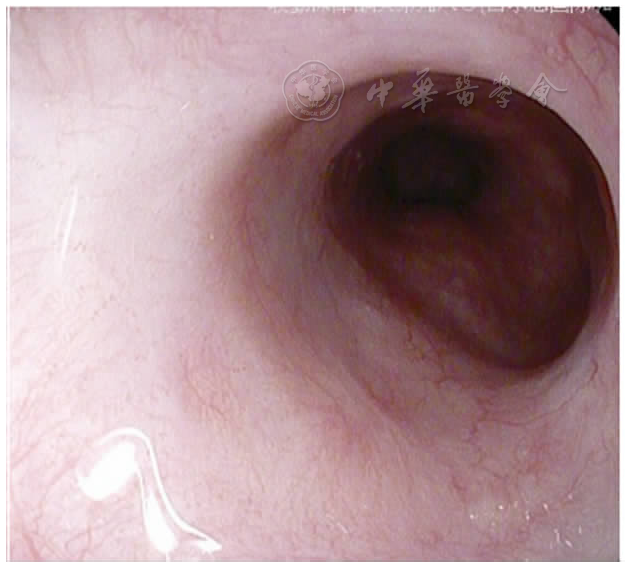

图5 喷射性出血

图6 气管插管后再次胃镜检查